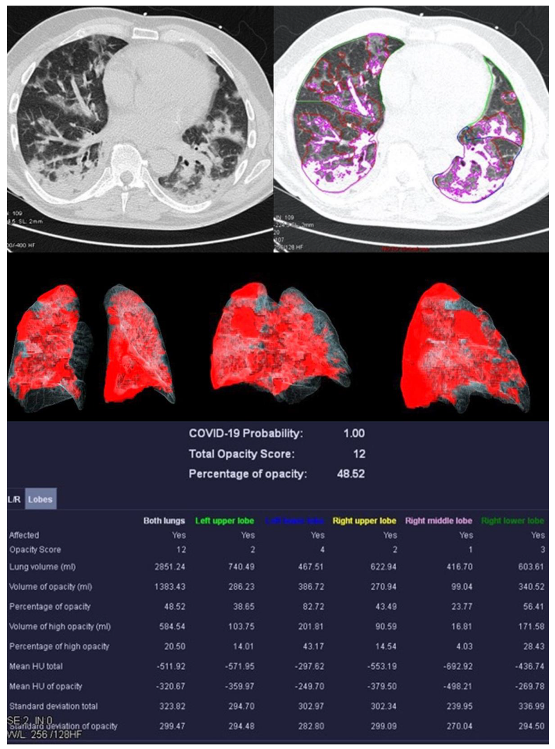

3.2. Image Analysis

| Mean COVID-19 Probability ± SD | 0.80 ± 0.36 | 0.33 ± 0.4 | 0.55 ± 0.47 | 0.66 ± 0.44 |

| Mean LSS ± SD | 8 ± 5 | 5 ± 4 | 5 ± 6 | 0 ± 0 |

| Mean PO ± SD in % | 26.39 ± 23.22 | 12.52 ± 17.97 | 18.90 ± 26.27 | 0.05 ± 0.12 |

| Mean PHO ± SD in % | 6.42 ± 7.68 | 3.60 ± 4.47 | 5.86 ± 10.04 | 0.01 ± 0.02 |